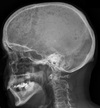

Patient presenting with hypercalcaemia

Multiple osteolytic lesions secondary to multiple myeloma Also know as 'rain-drop skull'